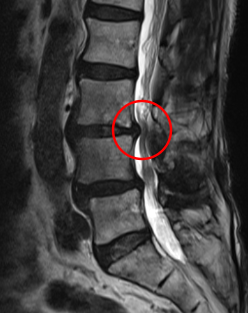

治療前

前回の治療時に発見していたL3/4の脊柱管狭窄症が悪化した可能性があると考え、再度、腰椎MRIで画像検査を実施しました。すると、元々、黄色靭帯が肥厚して狭窄を起こしていたL3/4で、それとは別に椎間板ヘルニアが進行しており、以前よりも狭窄が強くなっていることを確認しました。

なお、前回治療したL4/5はしっかりと減圧されていました。